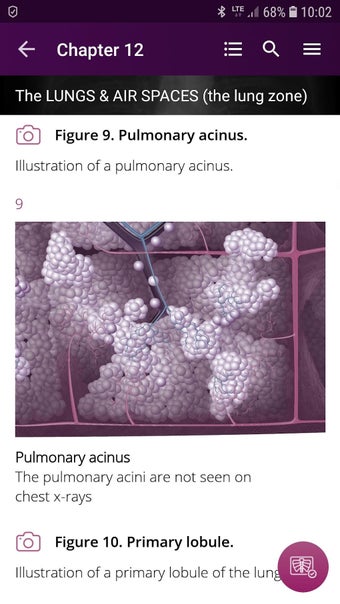

Radioloji'yi Keşfet: Göğüs Röntgeni Yorumlama, göğüs röntgeninin yorumlanmasının anlaşılmasını artırmak için tasarlanmış bir eğitim uygulamasıdır ve doktorlar, tıp öğrencileri ve radyologlar tarafından kullanılması amaçlanmaktadır. Uygulama, en küçük detayları görüntülemek için yakınlaştırılabilecek yüksek kaliteli görüntüler ve her bulgunun önemini anlamanıza yardımcı olacak bir sesli yorum içerir.

Uygulamanın amacı, kullanıcıların farklı x-ışını bulgularını ve bunların bir hastalığın teşhisinde nasıl kullanılabileceğini daha iyi anlamalarına yardımcı olmaktır. Uygulama, göğüs röntgeni yorumlaması için gerekli çeşitli yapı taşlarını kapsayan 5 bölüme ayrılmıştır.